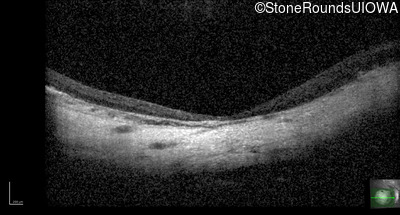

Age at visit: 15 years

This 15 year old male had a macular abnormality noted two weeks ago when he was refracted for his first pair of glasses. Bone spicule-like pigmentation was first noticed a year later (age 16) during a routine follow-up eye exam.